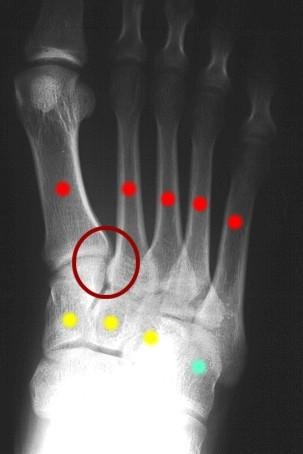

Figure 1: Normal AP xray of right foot. The yellow dots are the cuneiform bones (3). The red dots are the metatarsals (5). The teal dot is the cuboid bone. The red circle represents tthe Lisfranc joint between the 1st and 2nd metatarsals and the medial cuneiform bone.

Figure 2: Normal AP xray of right foot. The red circle represents the Lisfranc joint between the 1st and 2nd metatarsals and the medial cuneiform bone. Within this circle are the ligaments that are responsible for maintaining the stability of this key joint.

The bones consist of the 3 cuneiform bones and the cuboid bone. Further towards the toes, are the metatarsal bones. Everywhere that these bones come together, there is a joint. The proper alignment of the bones at the joints is due to the ligaments that hold the bones in the proper place. The Lisfranc joint actually refers to a number of joints which are formed by the junction of the metatarsals and the cuneiforms, and by the junction of the metatarsals and the cuboid bone.